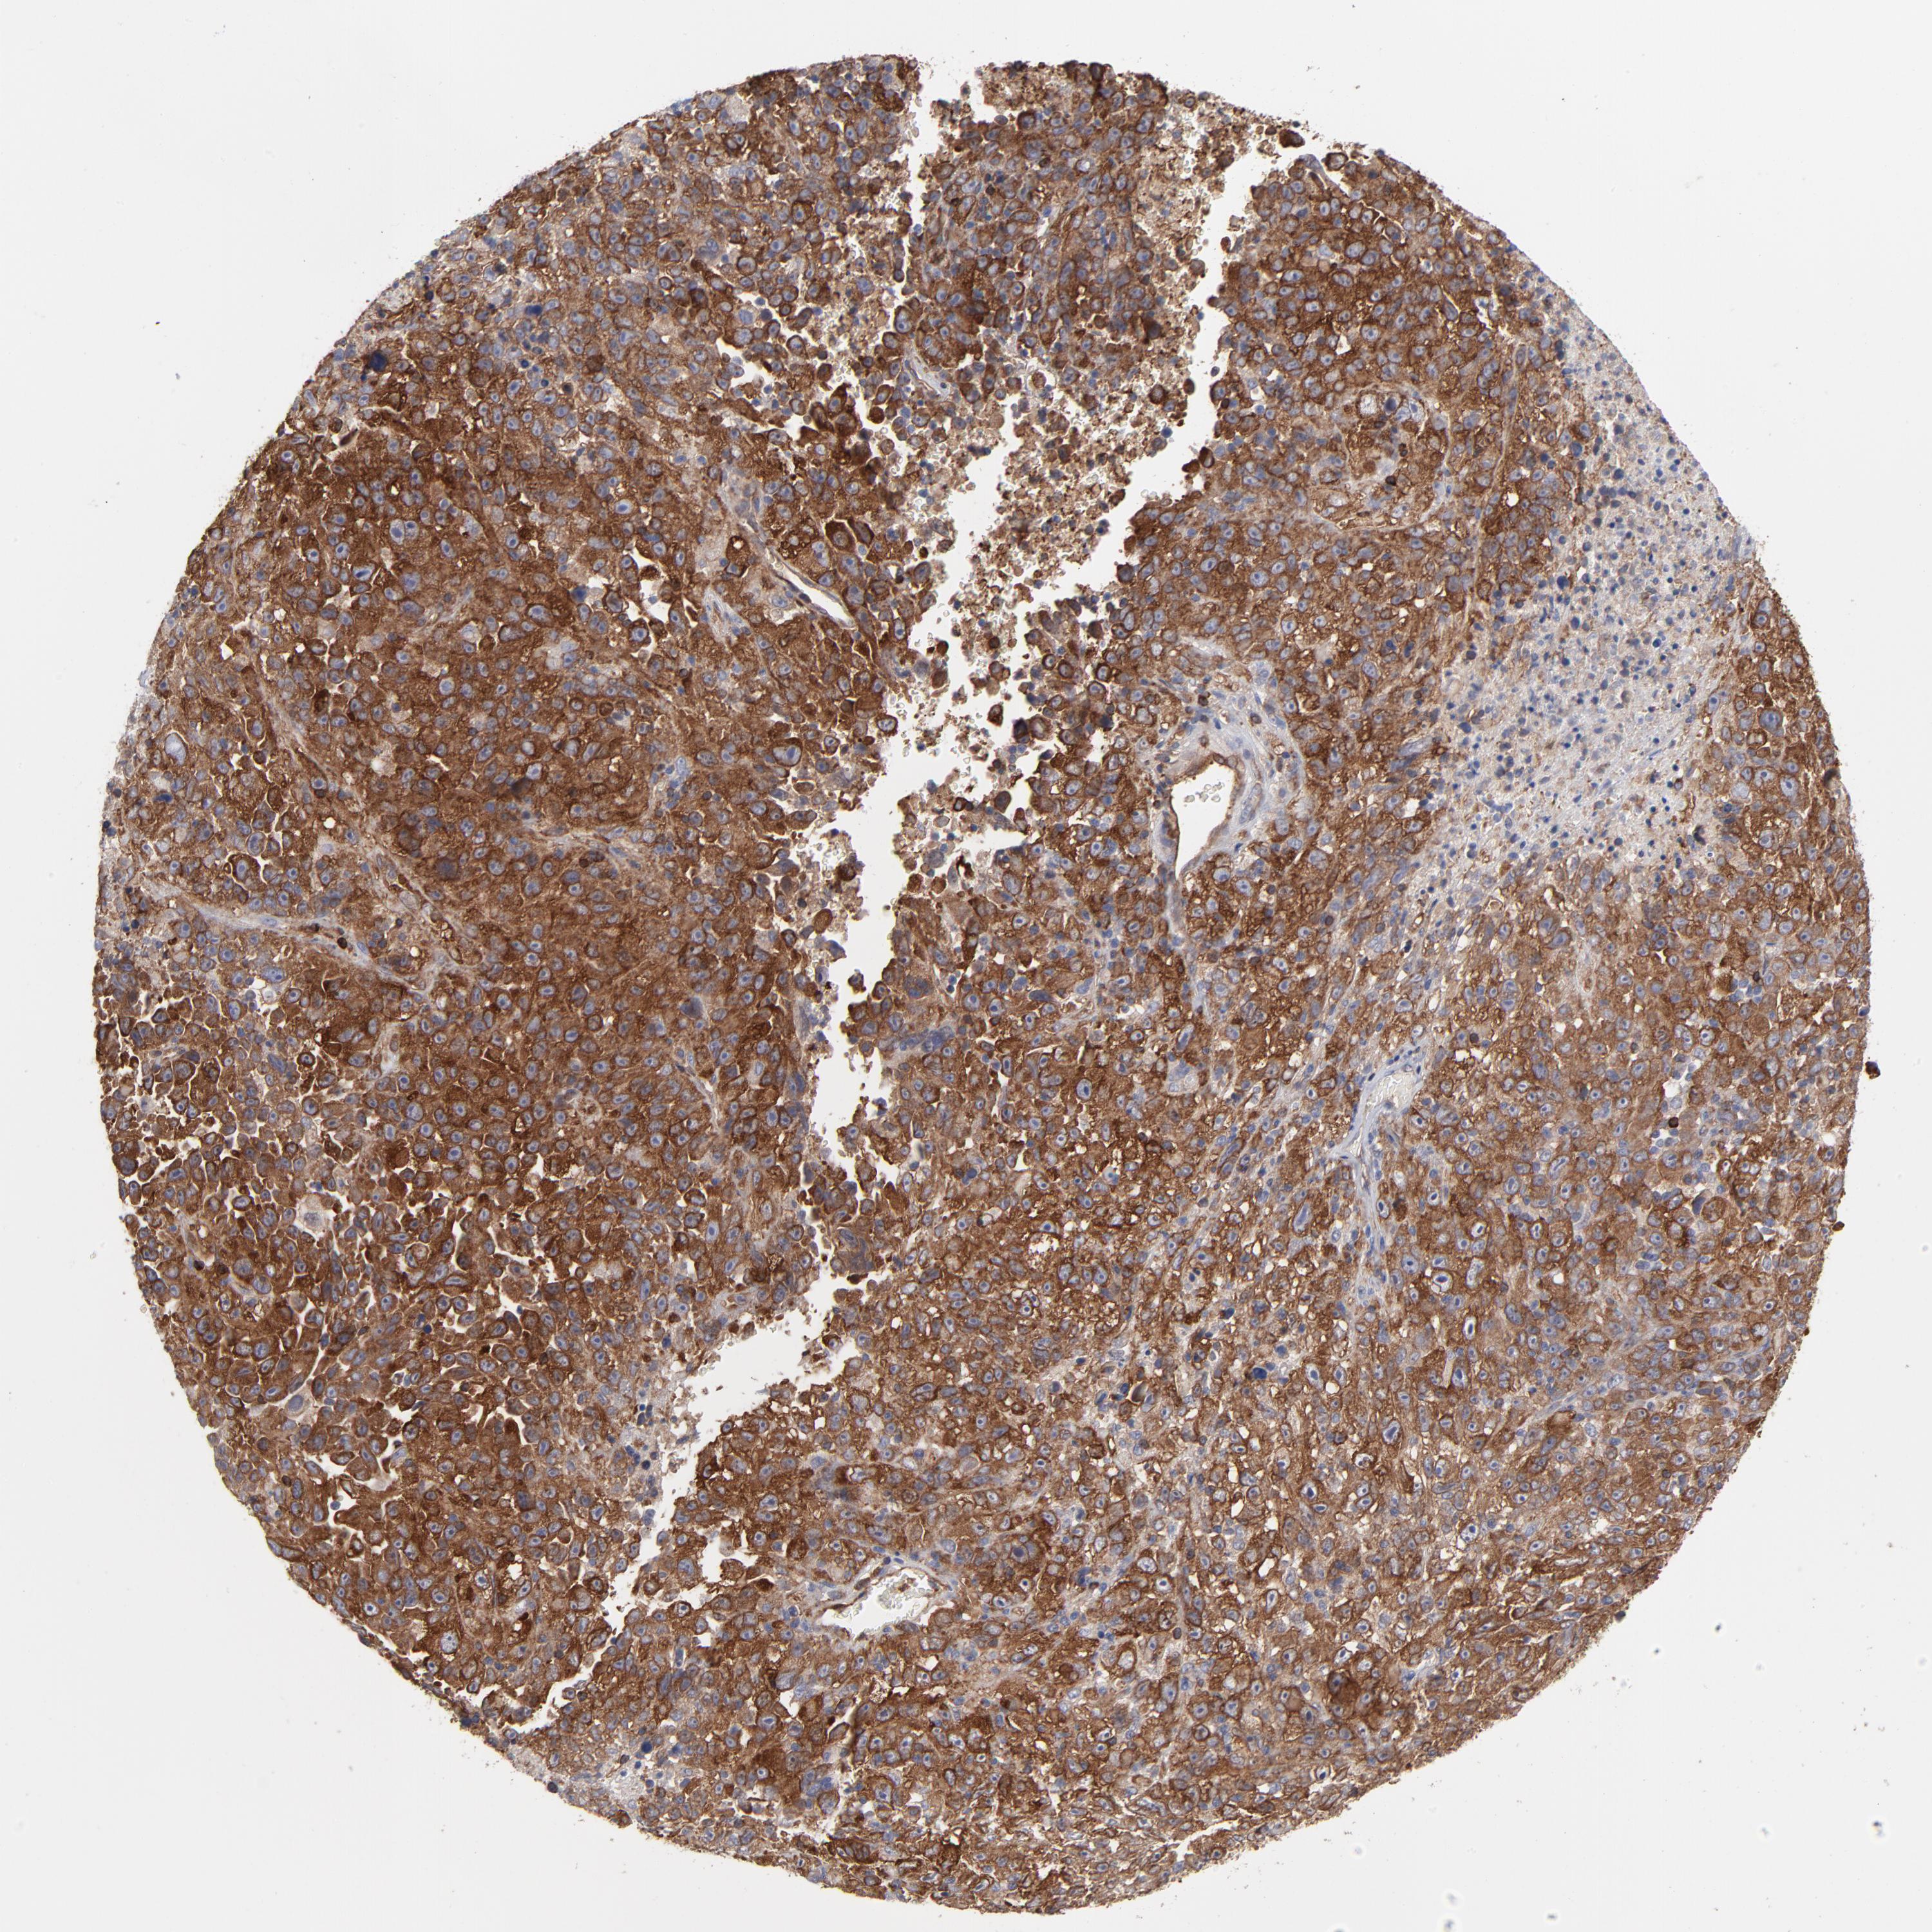

MELANOMA - Protein expressioni

A mouse-over function shows sample information and annotation data. Click on an image to view it in a full screen mode. Samples can be filtered based on level of antibody staining by selecting one or several of the following categories: high, medium, low and not detected. The assay and annotation is described here.

Note that samples used for immunohistochemistry by the Human Protein Atlas do not correspond to samples in the TCGA dataset.

Antibody stainingi

Antibody staining in the annotated cell types in the current human tissue is reported as not detected, low, medium, or high, based on conventional immunohistochemistry profiling in selected tissues. This score is based on the combination of the staining intensity and fraction of stained cells.

Each image is clickable and will lead to virtual microscopy that enables deeper exploration of all samples and also displays staining intensity scores, fraction scores and subcellular localization as well as patient and tissue information for each sample.

Antibody CAB003841

Staining

High

Medium

Low

Not detected

Intensity

Strong

Moderate

Weak

Negative

Quantity

>75%

75%-25%

<25%

None

Location

Nuclear

Cytoplasmic/membranous

Cytoplasmic/membranous,nuclear

Malignant melanoma, NOS

Malignant melanoma, Metastatic site